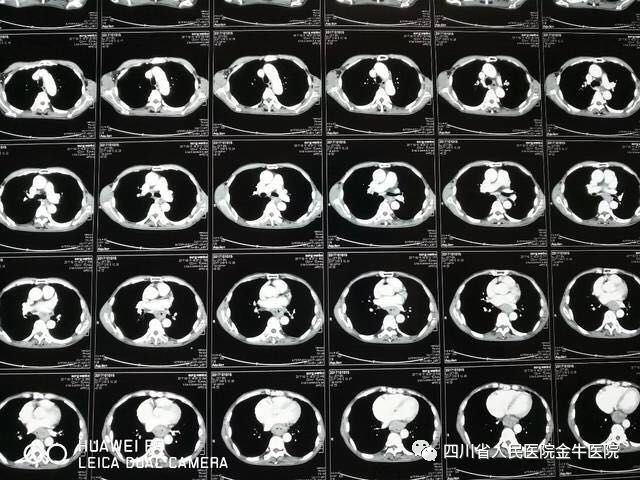

经过充分术前准备,手术如期进行。在手术室、麻醉科各科团队的配合下,历时7小时顺利完成了胸腹腔镜下食管癌切除、近端胃大部切除、淋巴结清扫及食管胃颈部吻合术,同时在腔镜下完成空肠营养管植入,为术后肠道营养提供了很好的通路。术后患者并发肺部感染,在我院及省医院ICU联合治疗后病情恢复顺利,术后我院行消化道造影检查未见吻合口瘘,逐步顺利进食,各种引流管按病程恢复情况顺利拔出,现已顺利出院,出院后定期复查即可。